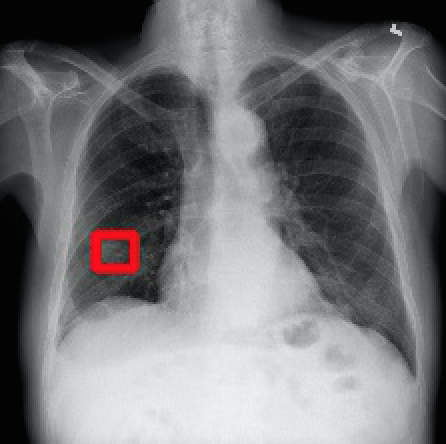

2017年CVPR的一篇“ChestX-ray8”论文[1]首次对医院留存的胸部CT数据库进行人工处理,并通过医学专家分别对8种疾病作标记,形成该领域首个标准的数据库,为胸部医疗的计算机辅助诊断打开了大门,也为后续的研究提供铺垫。CT数据库整理的效果如下图所示,其中红线框内为人工标注的疾病区域:

Atelectasis Cardiomegaly Effusion Infiltrate

Mass Nodule Pneumonia Pneumothorax

图2.1 胸部数据集示例

目前为止,数据集已经达到了14个疾病的分类结果,每张图的大小为1024×1024,少数图片附有由专家标注的病理区域,数据集共有112120张图片,来源于30805个不同的病人,其中51708张图片被标注有疾病,其余则为无病。可以看出无病的数据较多,对有病的特征学习可能较低,相关的学习加速收敛的方法将在2.4节讲解。